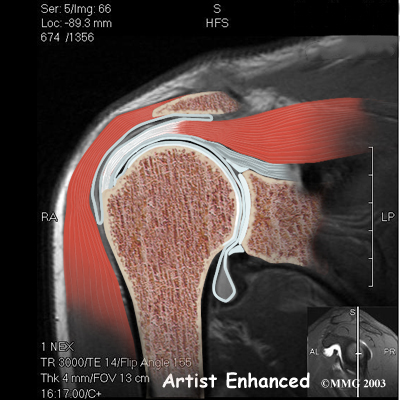

Physician Review

Your doctor may order X-rays to look for an abnormal acromion or bone spurs around the AC joint. A magnetic resonance imaging (MRI) scan may be performed if your doctor suspects a tear of the rotator cuff tendons. An MRI is a special imaging test that uses magnetic waves to create pictures that show the tissues of the shoulder in slices. The MRI scan shows tendons as well as bones. The MRI scan is painless and requires no needles.

Your doctor may order X-rays to look for an abnormal acromion or bone spurs around the AC joint. A magnetic resonance imaging (MRI) scan may be performed if your doctor suspects a tear of the rotator cuff tendons. An MRI is a special imaging test that uses magnetic waves to create pictures that show the tissues of the shoulder in slices. The MRI scan shows tendons as well as bones. The MRI scan is painless and requires no needles.